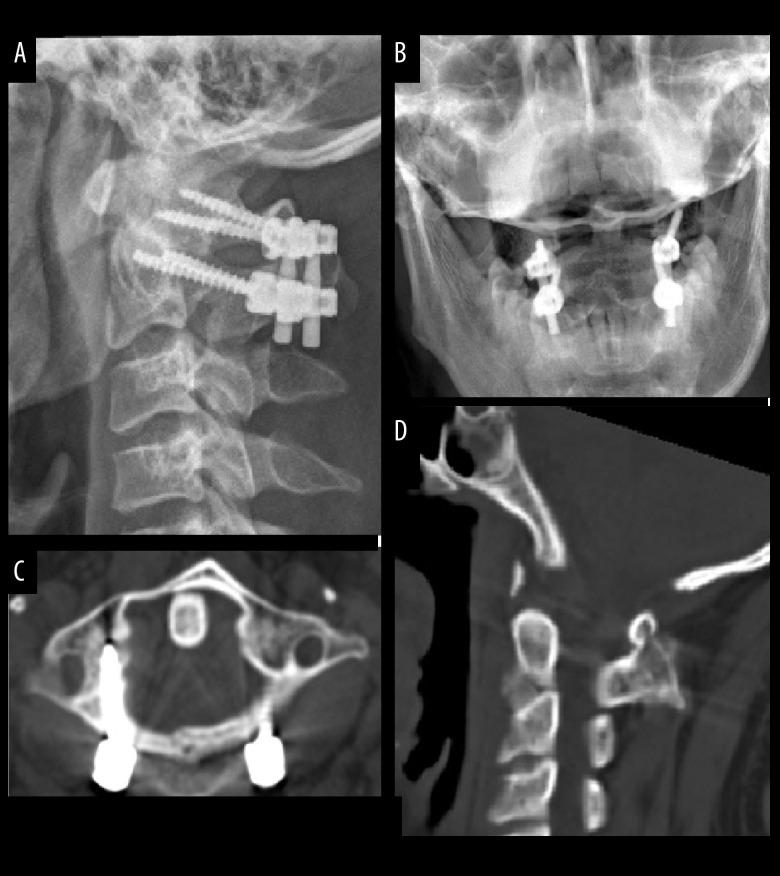

BACKGROUND Although most unstable C1 fractures can be effectively treated either by conservative treatment with external immobilization or by surgical procedure of C1-ring osteosynthesis, those fractures involving the lateral mass are likely to lead to traumatic arthritis and persistent neck pain. Specific reports of treatment of unstable C1 fractures involving the lateral mass are still scarce. We therefore present this report to evaluate the effectiveness of posterior C1-C2 screw-rod fixation and fusion for unstable C1 fractures involving the lateral mass. MATERIAL AND METHODS From June 2009 to June 2016 in our hospital, 16 cases were diagnosed with C1 fractures involving the lateral mass and treated by posterior C1-C2 screw-rod fixation and fusion from June 2009 to June 2016. The patients' clinical data were retrospectively analyzed. Preoperative and postoperative images were taken to evaluate cervical sequence, location of screws, and bone fusion. Neurological status and neck pain levels were evaluated clinically on follow-up. RESULTS All patients underwent surgery successfully. The mean follow-up duration was 15.3±4.9 months (range 9-24 months). All patients obtained satisfying clinical outcomes with good neck pain alleviation, appropriate screw placement, and reliable bone fusion. None of the patients developed vascular or neurological complications during the operation or follow-up. CONCLUSIONS Posterior C1-C2 screw-rod fixation and fusion is an effective management for unstable C1 fractures involving the lateral mass. This operation can provide reliable stabilization and satisfactory bone fusion.

在我们医院,自 2009 年 6 月至 2016 年 6 月,16 例诊断为涉及侧块的 C1 骨折患者,采用后路 C1-C2 螺钉-棒固定和融合治疗。回顾性分析患者的临床资料。拍摄术前和术后图像以评估颈椎序列、螺钉位置和骨融合情况。在随访时对神经状态和颈部疼痛水平进行临床评估。

所有患者均成功接受手术。平均随访时间为 15.3±4.9 个月(范围 9-24 个月)。所有患者均获得了满意的临床结果,颈痛缓解良好,螺钉放置适当,骨融合可靠。在手术和随访期间,没有患者发生血管或神经并发症。